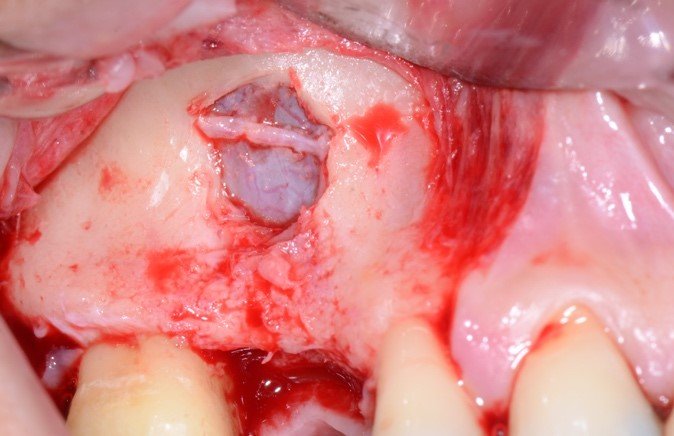

As figuras 16 e 17 mostram o transoperatório de um caso de hemorragia após dano a AAPS durante procedimento de osteotomia para rotação superior da janela óssea. A hemorragia durante a cirurgia trouxe dificuldades na visualização da membrana e a mobilização da janela para o interior da cavidade para formar o teto sobre a membrana sinusal. Somente após o preenchimento total com enxerto ósseo bovino particulado e cobertura com membrana hemostática de colágeno, houve diminuição do fluxo sanguíneo local. Mesmo com a manobra transoperatória, ocorreu a formação de extenso blefarohematoma periorbital e hematoma cérvico-facial. Segundo relato da paciente, o edema palpebral e na região parotídeo-masseterina provocaram dificuldade na abertura palpebral e bucal. As figuras 18 e 19 demonstram os hematomas já em regressão no 110 dia de pós-operatório (PO), já em uso de compressas mornas desde o 70 dia de PO, associado a moderada massagem local para drenagem hemo-linfática nos tecidos com pomada fibrinolítica.